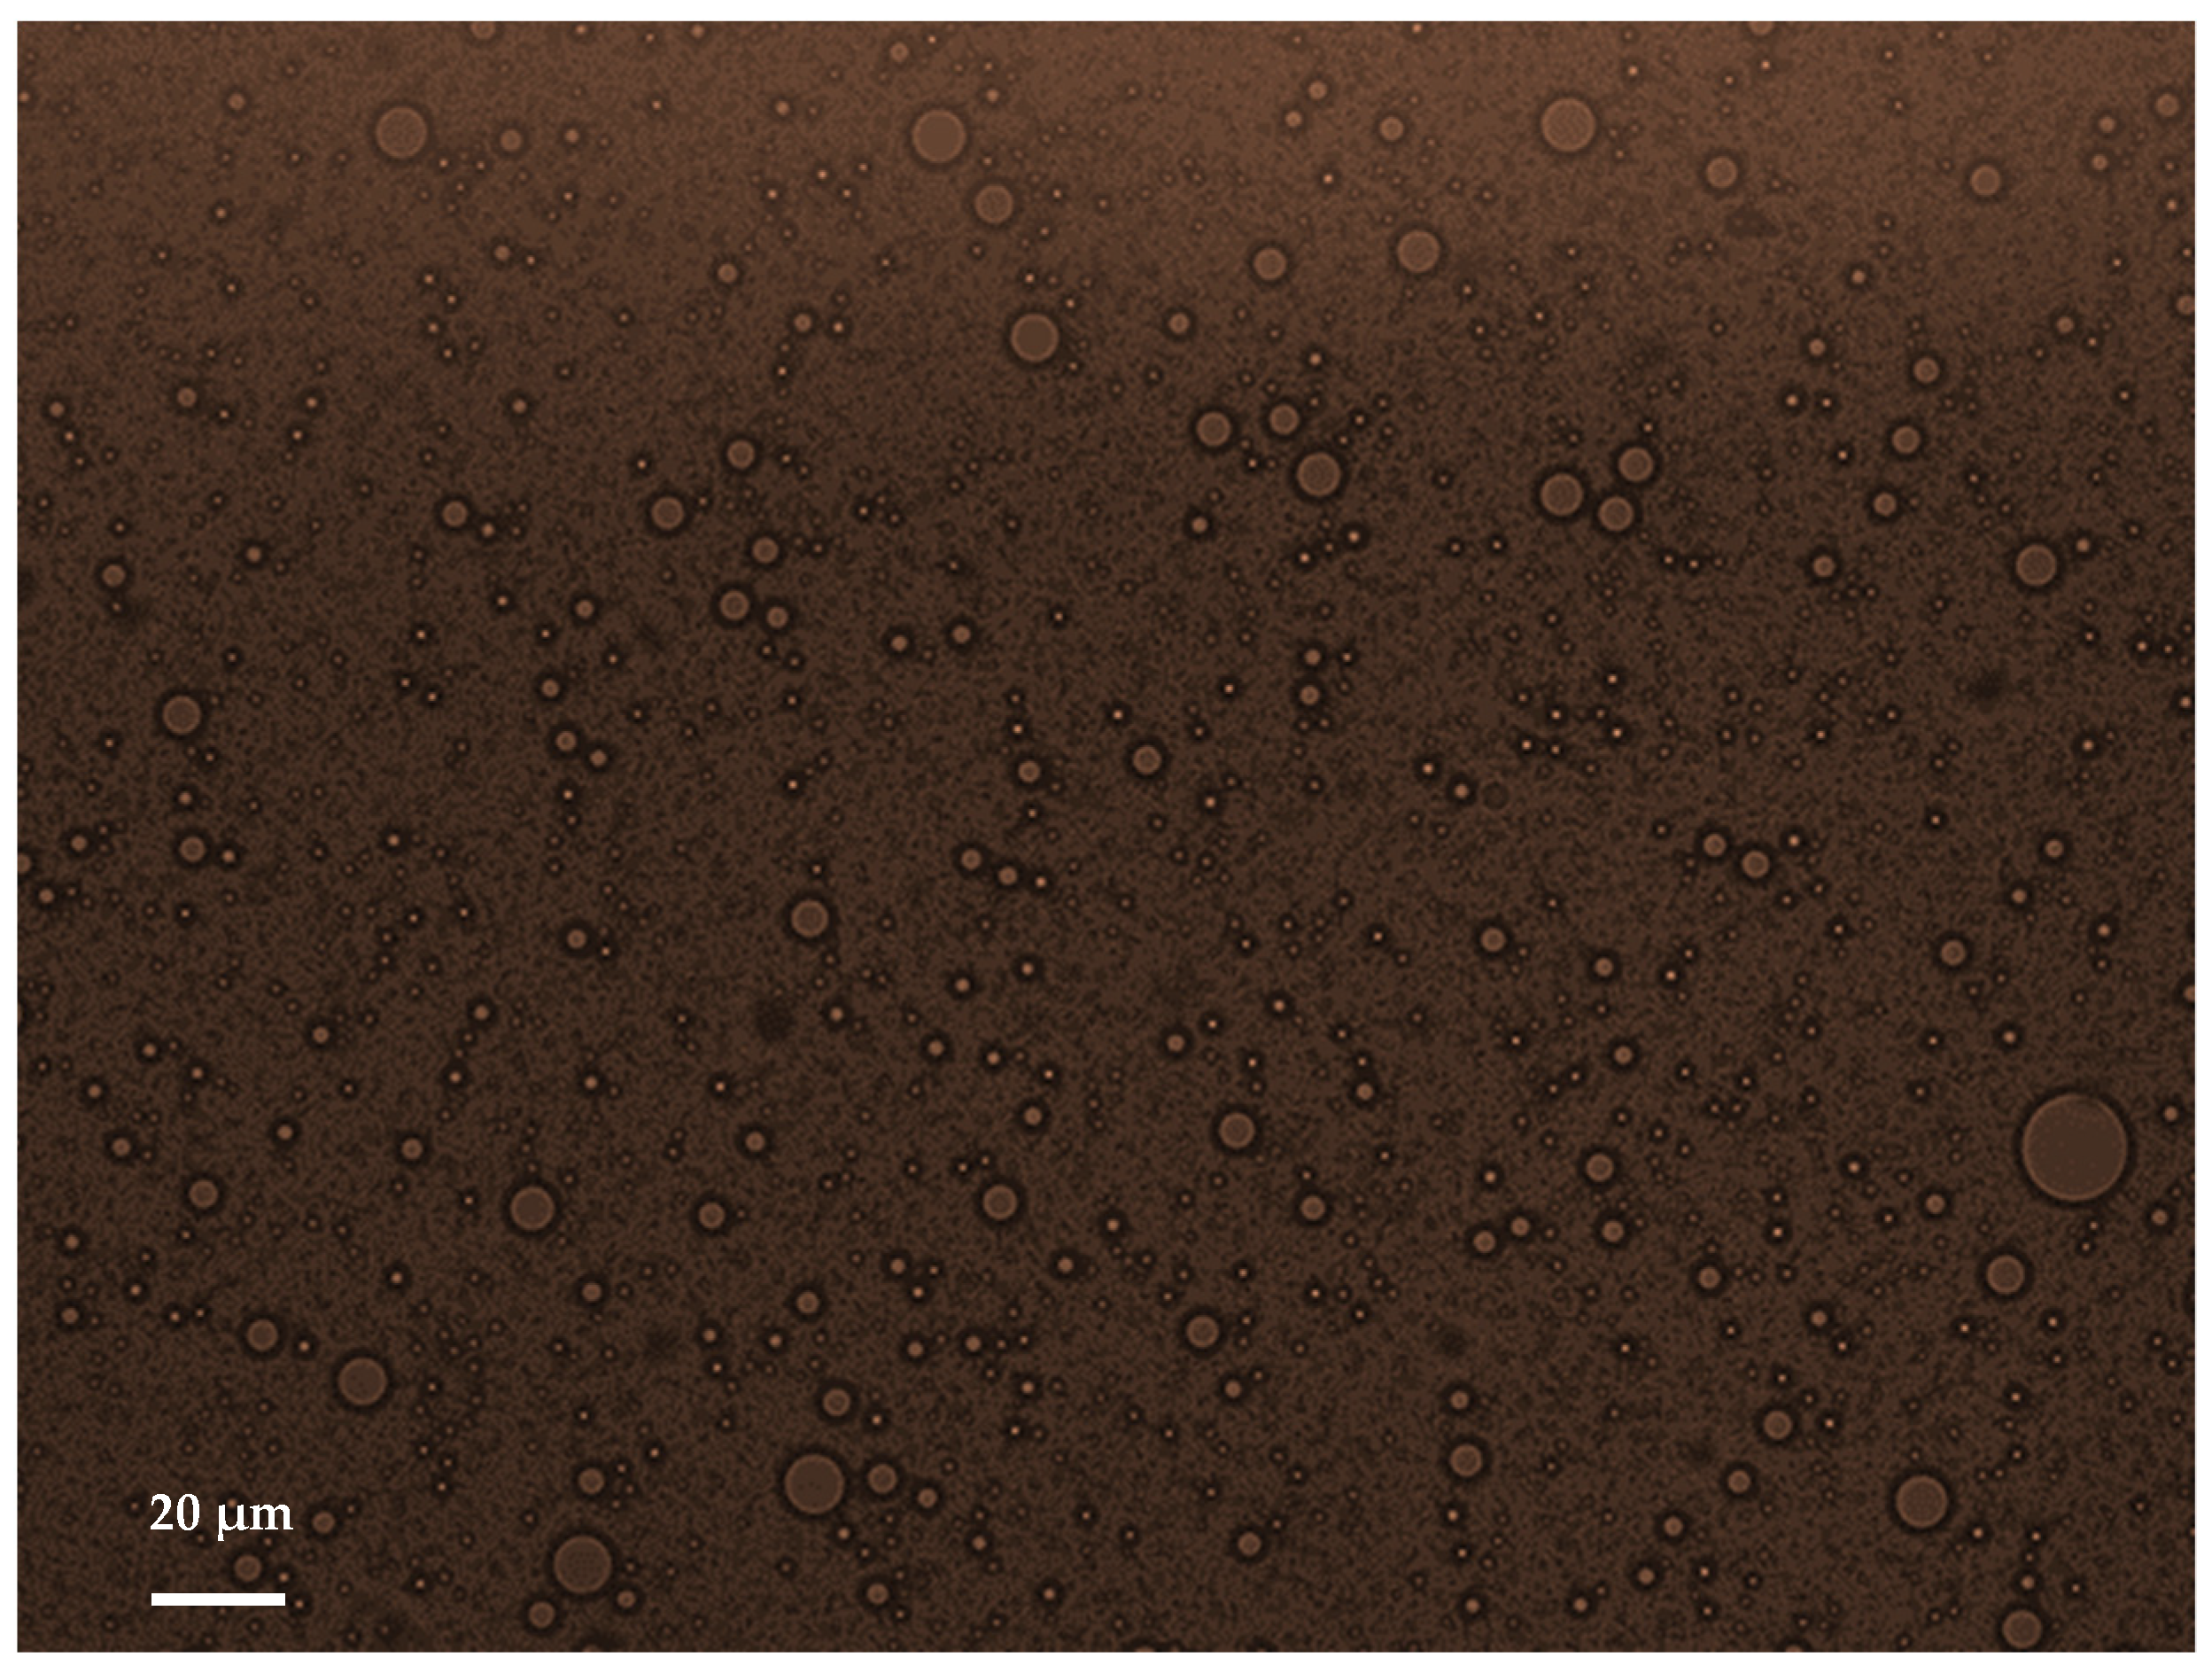

3.1. Characterization of the Droplets by Diffusion Light Scattering and Optical Imaging

| Mean diameter (µm) | 2.4 ± 0.4 | 2.0 ± 0.3 | 2.0 ± 0.1 | 1.9 ± 0.1 | 2.1 ± 0.1 | 1.9 ± 0.1 |

| DV50 (µm) | 3.6 ± 0.6 | 2.8 ± 0.5 | 2.3 ± 0.3 | 2.4 ± 0.3 | 2.2 ± 0.7 | 1.9 ± 0.2 |

| Number of droplets/mL | 7.6 × 107 | 7.1 × 107 | 7.1 × 107 | 8.7 × 107 | 8.0 × 107 | 10.0 × 107 |